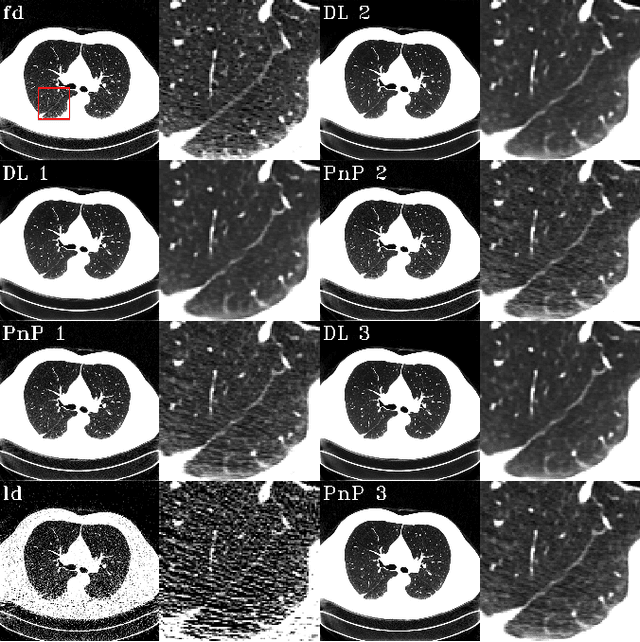

The Plug-and-Play (PnP) framework was recently introduced for low-dose CT reconstruction to leverage the interpretability and the flexibility of model-based methods to incorporate various plugins, such as trained deep learning (DL) neural networks. However, the benefits of PnP vs. state-of-the-art DL methods have not been clearly demonstrated. In this work, we proposed an improved PnP framework to address the previous limitations and develop clinical-relevant segmentation metrics for quantitative result assessment. Compared with the DL alone methods, our proposed PnP framework was slightly inferior in MSE and PSNR. However, the power spectrum of the resulting images better matched that of full-dose images than that of DL denoised images. The resulting images supported higher accuracy in airway segmentation than DL denoised images for all the ten patients in the test set, more substantially on the airways with a cross-section smaller than 0.61cm$^2$, and outperformed the DL denoised images for 45 out of 50 lung lobes in lobar segmentation. Our PnP method proved to be significantly better at preserving the image texture, which translated to task-specific benefits in automated structure segmentation and detection.